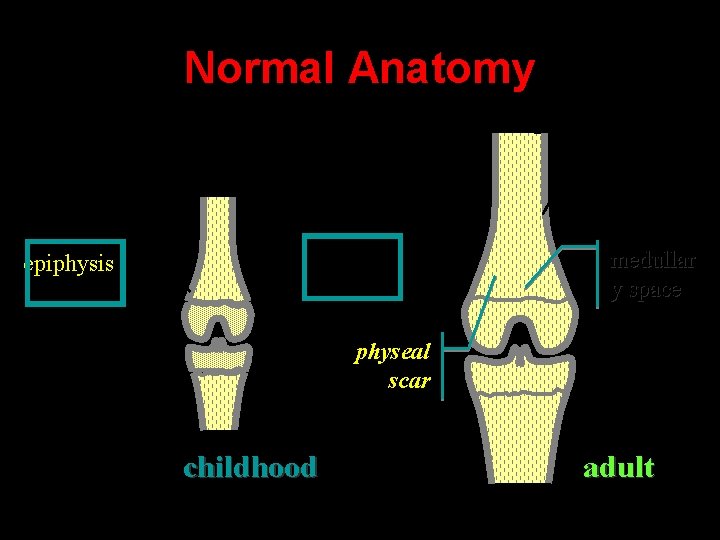

Normal Anatomy diaphysis cortex metaphysi s physeal physis scar epiphysis medullar y space METAPHYSIS childhood adult

Normal Anatomy diaphysis cortex metaphysi s epiphysis medullar y space physeal scar childhood adult